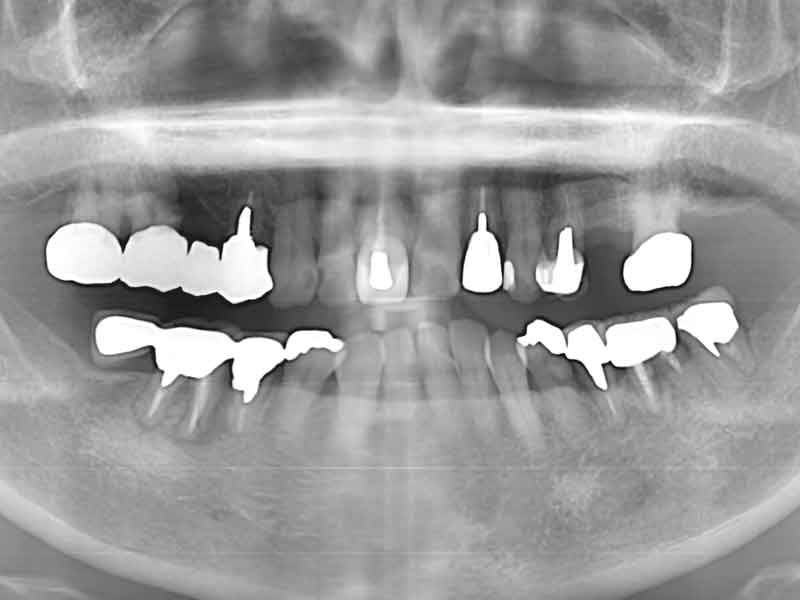

Before

術前

右下奥歯3本を治療

破折して保存不可能な歯根を抜いて、保存可能な歯根を残してブリッジを作成しました。

| ジルコニアブリッジ | 抜歯などの保険治療:約4,000円(税込) ジルコニアブリッジの費用:300,000円(税込) |

| 治療期間 | 2か月(抜歯後の歯茎の治癒を待つ期間を含む) |